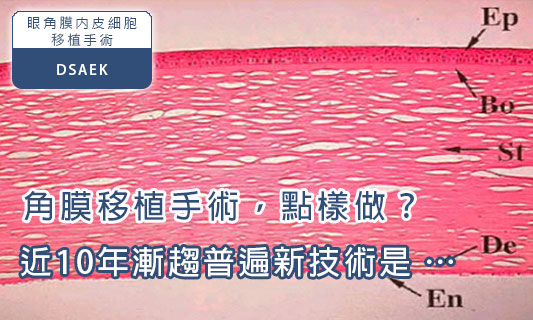

角膜移植是最常做的移植手術之一,最早期的角膜移植已有百年歷史,角膜移植的確為不少因角膜病變而導致失明的人重見光明。眼角膜共分五層,由面到底分別為表皮細胞層、前彈力層、基質層、後彈力層和內皮細胞層。

詳細內容